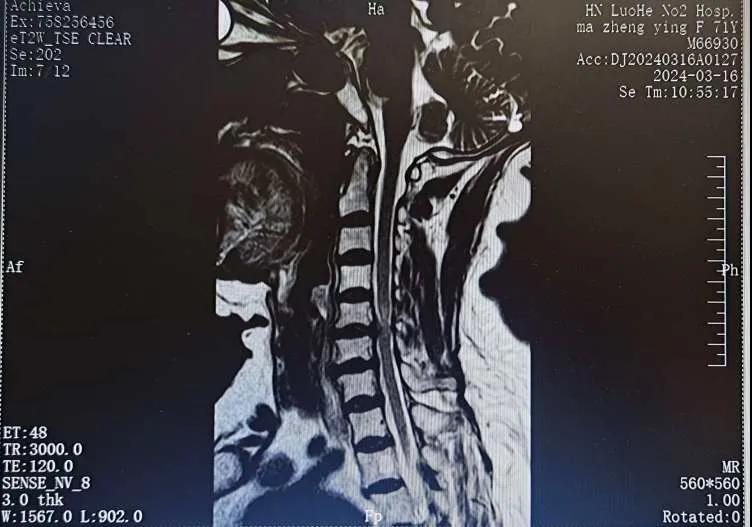

近日,70歲的馬阿姨,因摔傷后出現(xiàn)持續(xù)性頸部疼痛伴右側肢體無力、麻痛,影響日常生活。于是來到市二院神經外科就診,經檢查發(fā)現(xiàn):頸椎MR示:頸3/4、4/5、5/6、6/7椎間盤變性突出(中央型)并繼發(fā)性椎管變窄,頸椎退行性改變,頸5椎體水平頸髓水腫。神經外科副主任劉沛濤根據(jù)患者癥狀、體征、影像學三者結合診斷為“脊髓型頸椎病”,考慮到患者癥狀逐漸加重、保守治療效果不佳等情況,建議盡快手術治療。